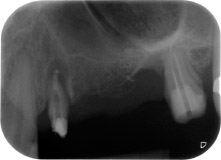

Eine 58-jährige Patientin, die auch eine gute Freundin und ärztliche Kollegin ist, beschwerte sich über Schmerzen und erhöhte Beweglichkeit ihres Brückenpfeilers 24. Es lag auch eine parodontale Entzündung vor, mit Taschentiefen von 7 mm mesiobukkal und mehr als 12 mm distal und einer Furkationsbeteiligung dritten Grades. Darüber hinaus zeigte die Röntgenaufnahme eine großflächige apikale Aufhellung am endodontisch (alio loco) vorbehandelten Zahn 24 (Abb. 1).

An der bukkalen Wurzel fehlte der gesamte vestibuläre und distale Knochen. Das Attachment beschränkte sich weitgehend auf die palatinale Wurzel, was die anfängliche schlechte Prognose unterstreicht. Auch Zahn 27 wies ein verringertes horizontales Attachment (vgl. Abb. 12) und eine kleine apikale Aufhellung (Abb. 1) auf, allerdings ohne klinische Symptome.